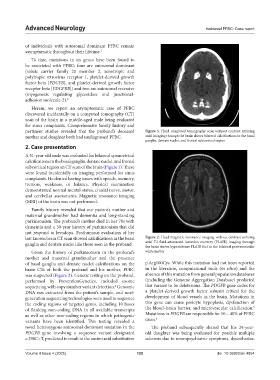

Herein, we report an asymptomatic case of PFBC

discovered incidentally on a computed tomography (CT)

scan of the brain in a middle-aged male being evaluated

for sinus complaints. Comprehensive family history and

pertinent studies revealed that the proband’s deceased Figure 1. Head computed tomography scan without contrast utilizing

mother and daughter both had undiagnosed PFBC. axial imaging through the brain shows bilateral calcifications in the basal

ganglia, dentate nuclei, and frontal subcortical region

A 51-year-old male was evaluated for bilateral symmetrical

calcifications in the basal ganglia, dentate nuclei, and frontal

subcortical region on CT scan of the brain (Figure 1). These

were found incidentally on imaging performed for sinus